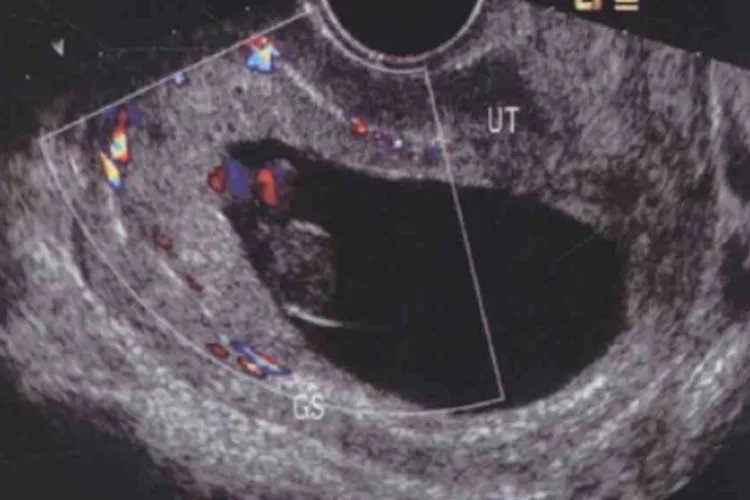

怀孕7个月的胎儿体重在1400-1500g左右,胎儿的头臀长在44cm左右,胎儿的双顶径约在7.2-7.9cm之间,胎儿的股骨长在5.6-6.0cm范围内,胎儿的腹围约在23-25cm之间,胎儿的皮下脂肪也开始形成。每个胎儿生长发育的快慢不一样,只要是在正常的范围,基本说明胎儿发育正常。怀孕7个月属于妊娠晚期,胎儿生长发育比较快,需要孕妇注意饮食的多元化,这样才能更好为胎儿生长发育提供营养物质,而且还需要多注意胎动情况,胎动的过于频繁或者突然不动就需要及时的去医院就诊。